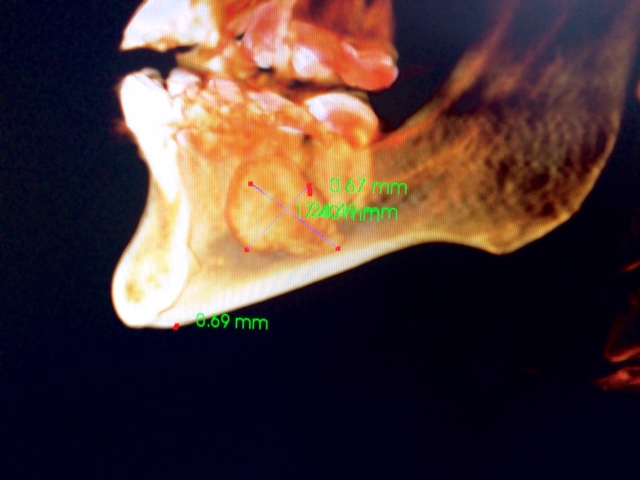

Head and Neck Tumor and Reconstruction

(cancer reconstruction)

Often after a patient has gone through various treatments for cancer there is a need that oral and maxillofacial services can provide for. In many cases, reconstructive surgery benefits patients having gone through specific skin cancers that are typically found in and around the head and neck regions. Depending on the severity and location of the cancer, skin cancer reconstruction options can range from simple to advanced procedures in order to restore both function and form.

The photos on this website are from real surgeries performed by Dr. Ulloa. Due to the

graphic nature of the images and content, viewer discretion is advised.